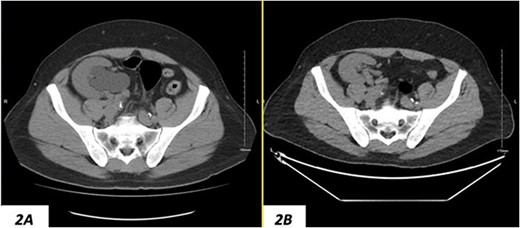

Despite a new onset proteinuria of 50 mg/dl, he continued to have a good functioning graft with a creatinine level of 93 μmol/l corresponding to an estimated glomerular filtration rate (eGFR) of 78 ml/min/1.73 m2. Nonetheless, he had also been noting an inguinal bugle that becomes more prominent as the day progressed, and it regressed at night. Upon further investigations, an ultrasound of the allograft revealed moderate-to-severe hydronephrosis. Further imaging using computed tomography scan (CT) confirmed the presence of upstream moderate hydronephrosis (Figs 1A and2A) along with a reported herniation of the ureter in a right inguinal hernia, resulting in a focal distal ureteric dilatation of 3.5 cm (Fig. 3A).

(A) Hydronephrosis of the allograft ureter on preoperative cross-sectional CT scan; (B) significant improvement of hydronephrosis on the 10-month postoperative image.